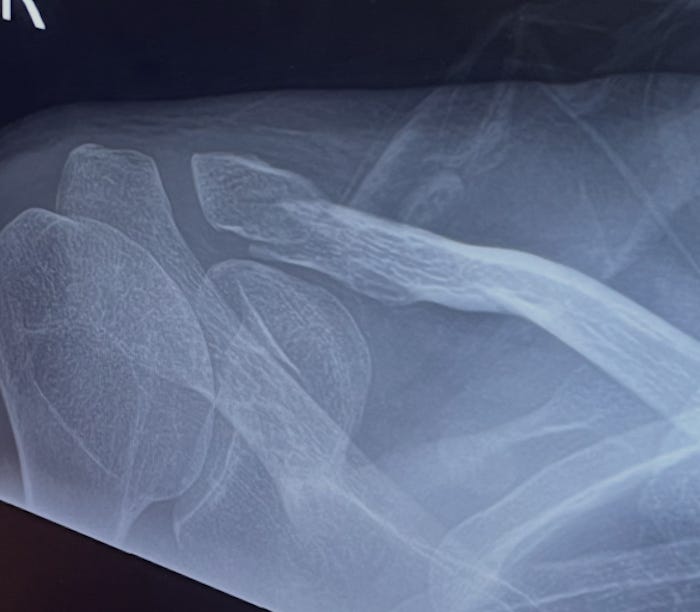

One porter tells another, “If you’re in there, you’re there.” An old woman looks at me benevolently. I’m in this gooey dreamscape prickled with nausea for about forty minutes before I remember that I need to tell someone why I’m there. The X-ray confirms the break. My arm is nestled in a fetching blue sling. Another nurse wolf-whistles at my X-ray. “You’ve done it!” she calls down the hallway. I remember I was trying to cook up a metaphor about existence itself being a long hallway between two doors at this point and thinking I’d probably stolen it from Beckett. The nurse tells me I’ll get a call about a follow-up appointment but nobody can tell me when that might be. “There’s no Caller ID,” she says with a Wonderland grin that acknowledges the lunacy of the situation without trashing it, “so a lot of people, they never answer the call, never show up.”

I ask Moritz if it’s a clean break. He says, “Clean is not a word we like terribly much in orthopedics because it implies dirt or infection at the site of the injury. The bone did not pop out. There is no evidence of infection.” He says, “You seem a reasonably happy bunny to me.” I nod. “We talk in bones about displacement,” he points to the fracture on the X-ray with his pen. “You can see here,” he says, “where things, they are displaced.”

The monster purrs under my skin: he goes to sleep but he doesn’t disappear. This morning in the mirror, the bruise was dark purple, like a storm cloud. Now, I stare at my bone on the screen. It glows.